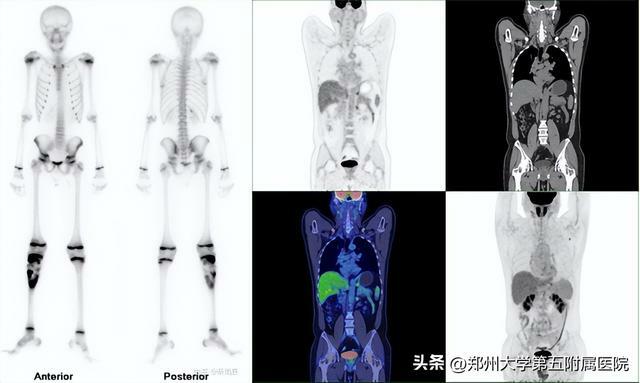

05核醫學

核醫學是應用放射性核素或核射線診斷、治療疾病或進行醫學研究的學科。大致分為實驗核醫學和臨床核醫學兩部分。

1診斷核醫學

包括臟器或組織影像學檢查、臟器功能測定和體外分析等。醫生根據檢查目的,給病人口服或靜脈注射某种放射性示蹤劑,使之進入人體後參與體內特定器官組織的循環和代謝,並不斷的放出射線。這樣我們就可以在體外用各種專用探測儀器追蹤探查,以數字、圖像、曲線或照片的形式顯示出病人體內臟器的形態和功能。

核醫學影像檢查有輻射!